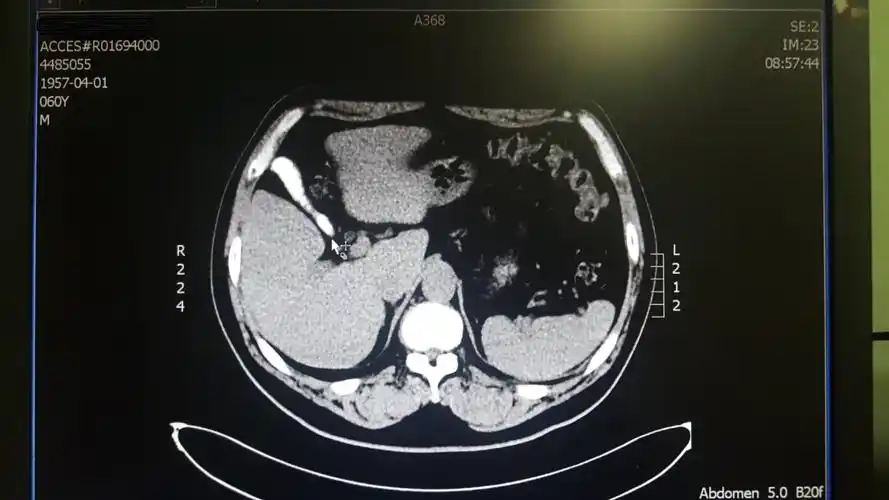

腹部ct提示:胆囊结石(箭头处)

ct横断面可见结石自下而上填满胆总管.